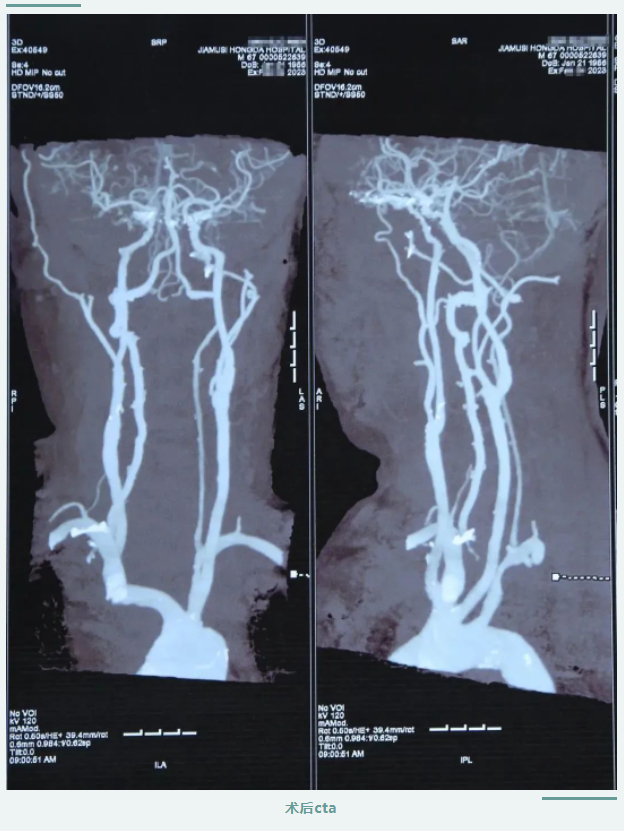

在醫(yī)護(hù)人員及患者家屬的精心照料下,患者術(shù)后狀態(tài)恢復(fù)良好,頭暈及肢體乏力明顯改善,肢體恢復(fù)知覺、可自主活動(dòng),言語清晰,感覺良好。

頸動(dòng)脈內(nèi)膜剝脫手術(shù)的順利完成,是我院在腦血管病治療中取得的新突破,填補(bǔ)了我院頸動(dòng)脈剝脫手術(shù)技術(shù)空白,對(duì)于腦卒中的預(yù)防和治療具有重要作用,標(biāo)志著我院腦血管病診療技術(shù)再上新臺(tái)階。